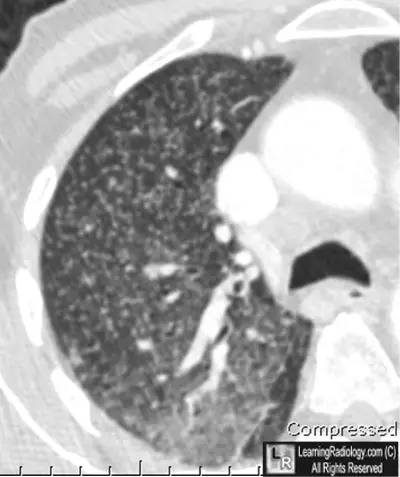

胸部CT轴位扫描

右胸CT轴位扫描特写

上图:两肺弥漫性粟粒结节

下图:局部特写图(白圆圈内)